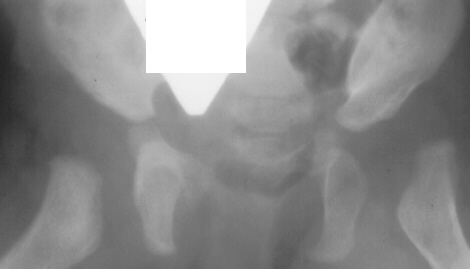

Femoral

heads which show the head-within-head appearance have a better

prognosis.